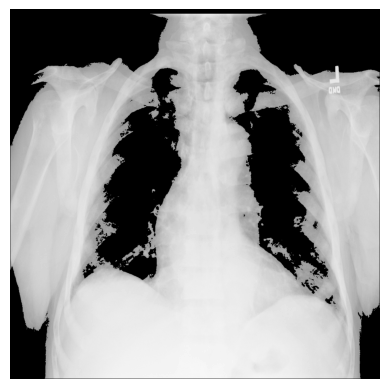

使用 np.where() 对 X 射线图像应用掩码

为了仅筛选出 X 射线图像中的特定像素以帮助检测特定特征,可以使用 NumPy 的 np.where(condition: array_like (bool), x:array_like, y: ndarray) 应用掩码,当条件为 True 时返回 x,否则返回 y。

识别感兴趣的区域 - 图像中的某些像素集合 - 可以很有用,掩码是与原始图像形状相同的布尔数组。

3. 您可以使用 NumPy 的 np.where() 创建不同的条件掩码 - 例如,让我们只有那些像素超过某个阈值的图像值:

# 阈值为“大于 150”

# 如果为真,则返回原始图像,否则返回 `0`

xray_image_mask_noisy = np.where(xray_image > 150, xray_image, 0)

plt.imshow(xray_image_mask_noisy, cmap="gray")

plt.axis("off")

plt.show()

# 阈值为“大于 150”

# 如果为真,则返回 `1`,否则返回 `0`

xray_image_mask_less_noisy = np.where(xray_image > 150, 1, 0)

plt.imshow(xray_image_mask_less_noisy, cmap="gray")

plt.axis("off")

plt.show()